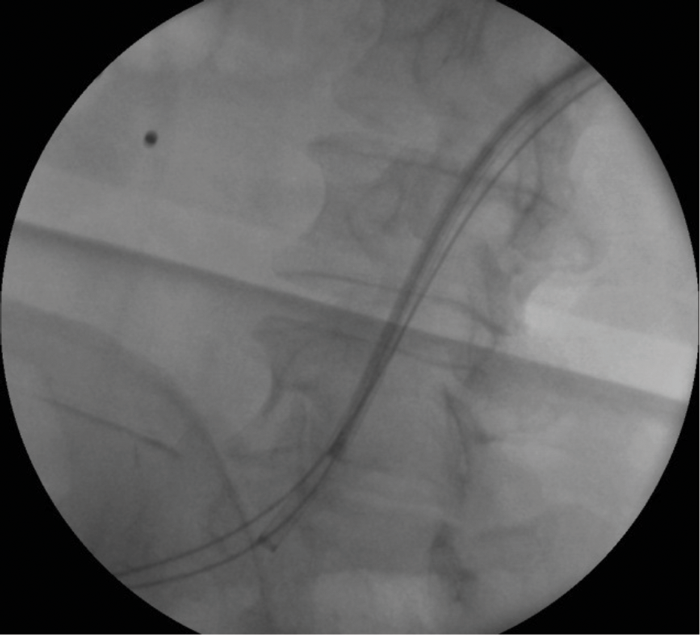

Figure 2: Fluoroscopic image during procedure.